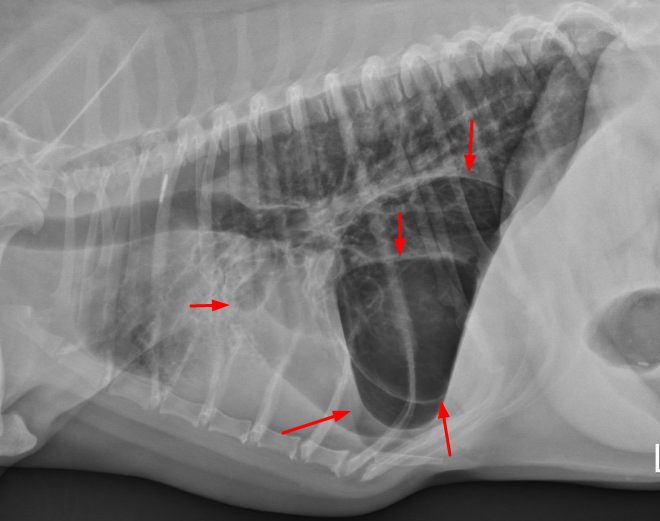

임상적 의미가 있는 bulla는 아래와 같이 방사선 상에서 도 보일 정도로 심각한 크기의 bullar여야 의미를 갖는다.

마취전검사에서 저런 수준의 bullar가 아니라면

bullar 자체가 마취에 영향을 주지 않는다는게 이 논문이 말하고자 하는 부분이다.